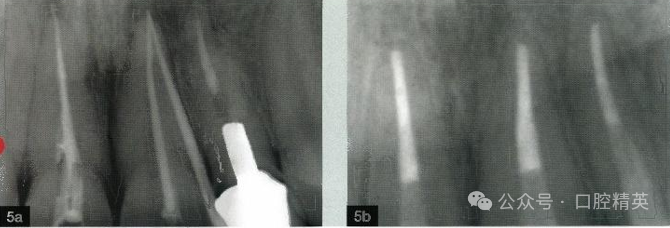

图:5a,b 掌握不同的根管充 填技术,以取得理想的短期和长期效果。